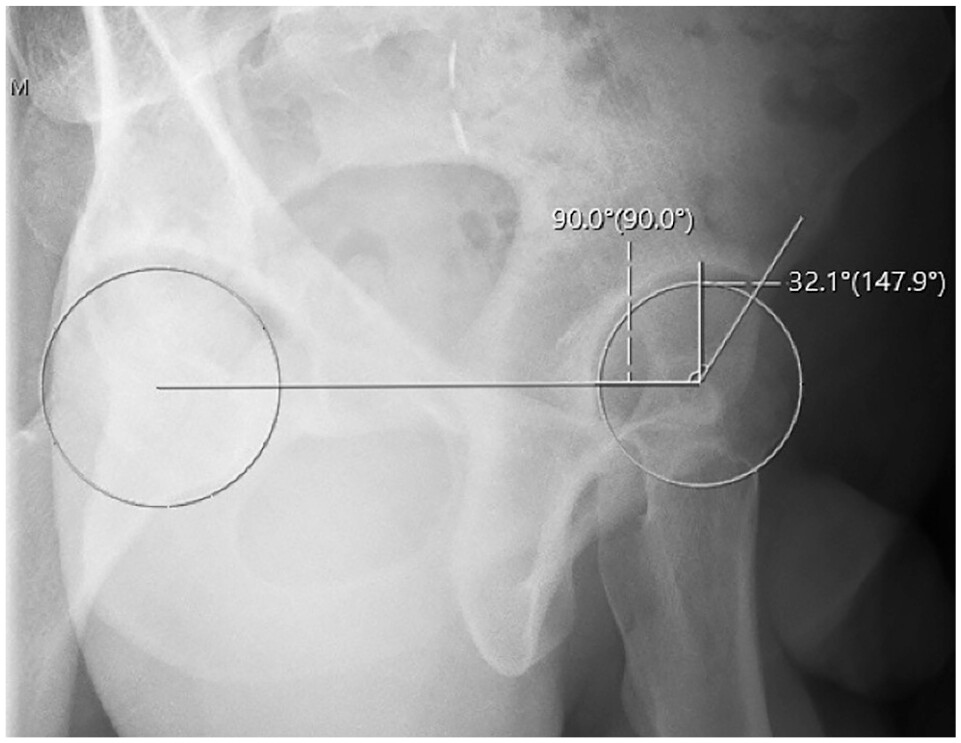

A group led by orthopedic surgeons at the University of Texas Southwestern Medical Center in Dallas tested an algorithm (IB Lab HIPPO, Image Biopsy Lab) in 130 patients with hip dysplasia compared with measurements by three trained readers. The algorithm performs six measurements associated with hip dysplasia.

Among 256 hips with AI outputs, all six hip AI measurements were successfully obtained, according to the study. The AI-reader correlations were generally fair to excellent, with the most widely used measurements for hip dysplasia diagnosis (lateral center edge angle and Tönnis angle) demonstrating good to excellent intermethod reliability.